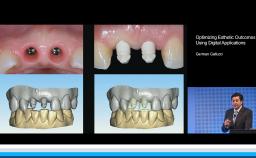

Dr. Gallucci is the Chair of the Department of Restorative and Biomaterial Siences at Harvard School of Dental Medicine. ITI Fellow since 2004, Chair of the ITI Scholarship Center at Harvard.

ITI Study Club UIC Chicago - Lecture with Dr. German Gallucci - “Implant-Prosthodontic Integration in the Esthetic Area”